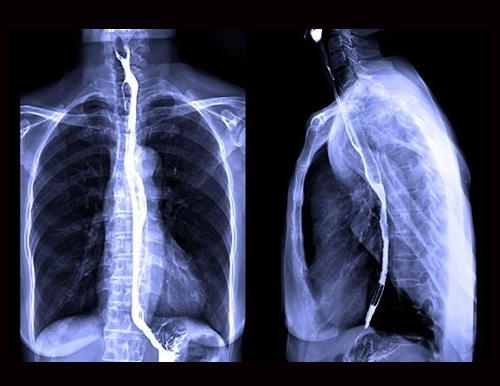

Barium Procedures

The radiologist will ask you to take a swallow of a thick, chalky barium drink. The barium is usually flavored, but it may not taste very good. As you swallow the barium, the radiologist will take single pictures, a series of X-rays, or fluoroscopy to watch the barium moving through your mouth and throat.